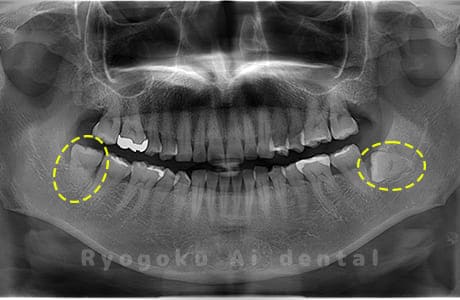

Case04

- 原因

- 上顎の親知らず、下顎の水平埋伏の親知らず

- 治療内容

- 上顎の親知らず、下顎の水平埋伏の親知らずを抜歯したケースです。

<リスク・副作用>

手術後は痛み、腫れ、痺れなどの副作用が生じる場合があります。